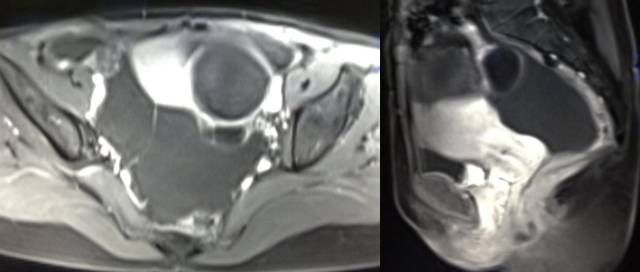

MR检查:

病理结果:黄体血肿

黄体血肿为正常排卵过程中,卵泡层破裂,引起出血,较多的血液潴留在卵泡或黄体腔内形成血肿。

正常黄体直径为15mm左右,以后转变为白体,并在下一个周期的卵泡期自然消退。若黄体内出血量较多,则形成黄体血肿,或称黄体内出血,出血性黄体。黄体血肿多为单侧,一般直径为40mm,偶可达100mm,黄体血肿被吸收后可导致黄体囊肿,较大的血肿破裂时可出现腹腔内出血,剧烈腹痛、少量阴道流血和腹膜刺激征,不易与宫外孕区别。

根据时间不同MR信号也有所不同,TIWI脂肪抑制序列可以鉴别脂肪和出血。

卵巢囊肿:呈均匀的T1WI 低信号,T2WI 高信号,边界清楚,壁薄,大多数病灶直径≤5 cm,但囊肿的起源及定性诊断困难。

巧克力囊肿:常呈多发的单囊或多囊改变,病灶大小不等,囊壁厚薄不均,囊内信号复杂,囊内或各囊腔间血液因出血时期不同,信号常呈多样性,囊肿内反复出血、破裂,形成相互粘连的多房性囊肿,是其较为特征性的表现。

在鉴别卵巢畸胎瘤、出血性囊肿或巧克力囊肿时,MR 脂肪抑制T1WI 可明确肿块内高信号成分是脂肪还是出血,同时由于脂肪组织与非脂肪组织的共振频率不同,在两者交界处沿磁场频率编码方向出现化学位移伪影,但出血性囊肿与巧克力囊肿的鉴别有时较为困难。